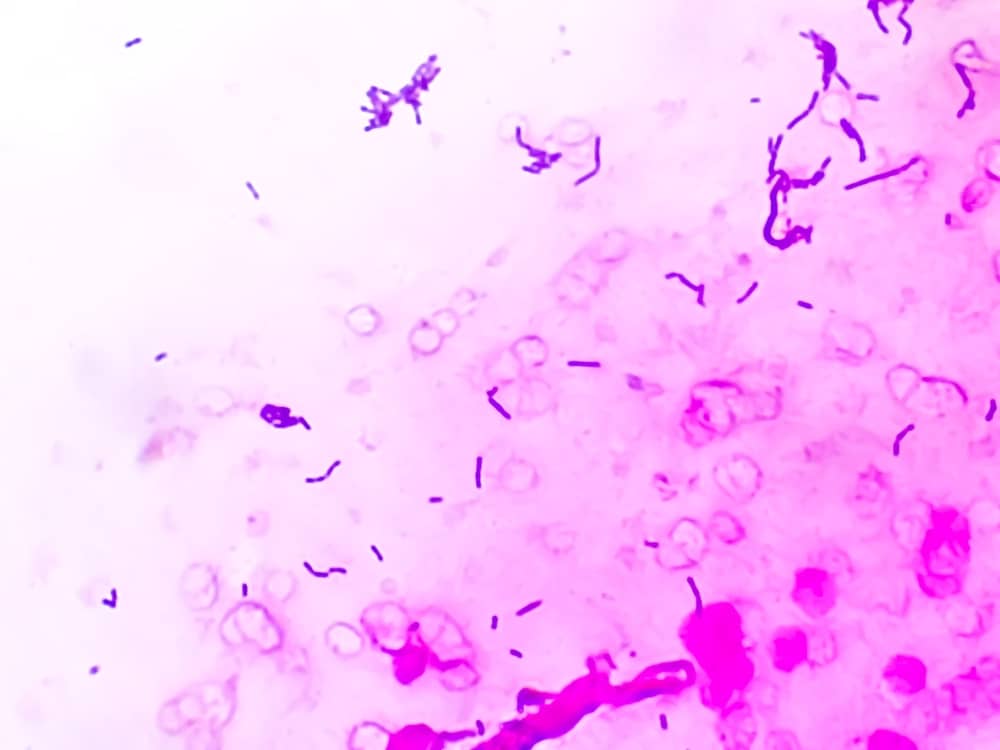

Khi quan sát dưới kính hiển vi kỹ thuật viên có thể thấy vi khuẩn lạ xuất hiện dẫn đến nhầm lẫn giữa gram dương và gram âm hoặc phát hiện vi khuẩn không có thật trong bệnh phẩm.

Những vi khuẩn này sau đó bám vào slide mới trong quá trình ngâm, tạo ra vi khuẩn ma trên kính hiển vi. Tạp khuẩn loại 2 thường gây ra tình trạng nhuộm không đồng đều, màu sắc bị lẫn lộn hoặc xuất hiện vi khuẩn lạ không thuộc mẫu bệnh phẩm.

Kết quả gram dương hiển thị màu tím đặc trưng và gram âm hiển thị màu đỏ rõ nét dưới kính hiển vi. Máy còn giảm đáng kể tiếp xúc với hóa chất nguy hiểm nâng cao an toàn cho nhân viên lab. Với thiết kế đơn giản chỉ cần xếp slide vào khay và bấm nút là hoàn tất bất kỳ ai cũng có thể sử dụng mà không cần đào tạo phức tạp.